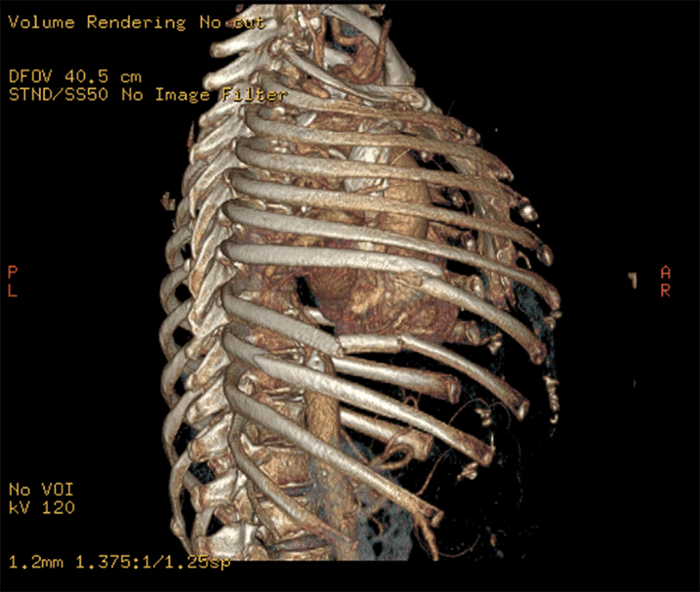

Figure 6. CT 3-D Reconstruction of Chest Wall Deformity. Published with Permission

On arrival at our hospital, the patient had severe subcutaneous emphysema. She was hemodynamically normal, saturating 95% on a 3 L nasal cannula. Her imaging revealed comminuted and displaced fractures of right-sided ribs 7 through 9 (Figures 1, 2, and 3).

The patient was taken to the operating room. She had an obvious area of contusion and deformity over ribs 7, 8, and 9 (Figure 6). We proceeded to make a small anterolateral thoracotomy incision over that area. The lung reduced back into the pleural cavity on our initial assessment. For rib fixation (Figure 7), we used 20-hole plates. A 32 French chest tube was placed under direct vision into the pleural cavity. Finally, we used several #1 Vicryl sutures to approximate the defect between ribs 7 and 8 to avoid future lung herniation.